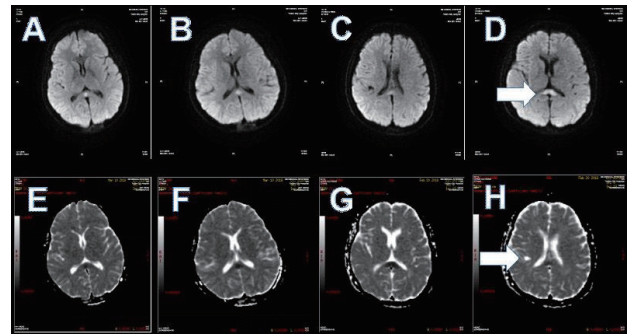

磁共振提示胼胝体局灶病变多为轻症患者(图 3);磁共振提示胼胝体双侧放射冠部散在病变多为中型患者(图 4);磁共振提示胼胝体双侧放射冠区弥漫性病变多为重症患者(图 5,6)。

| 图 3 ABCD为同例患者,病变为胼胝体局灶病变(箭头所示);EFGH为同例患者,病变为胼胝体右侧放射冠区局灶病变(箭头所示) |